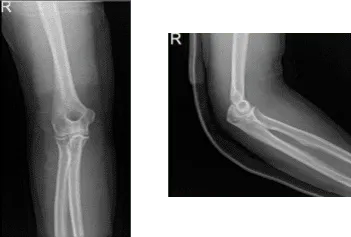

Tras la cirugía, el paciente fue atendido para una revisión de seguimiento y presentó un resultado de radiografía del codo derecho que mostró radiografías normales del codo derecho.

Radiografía del codo derecho